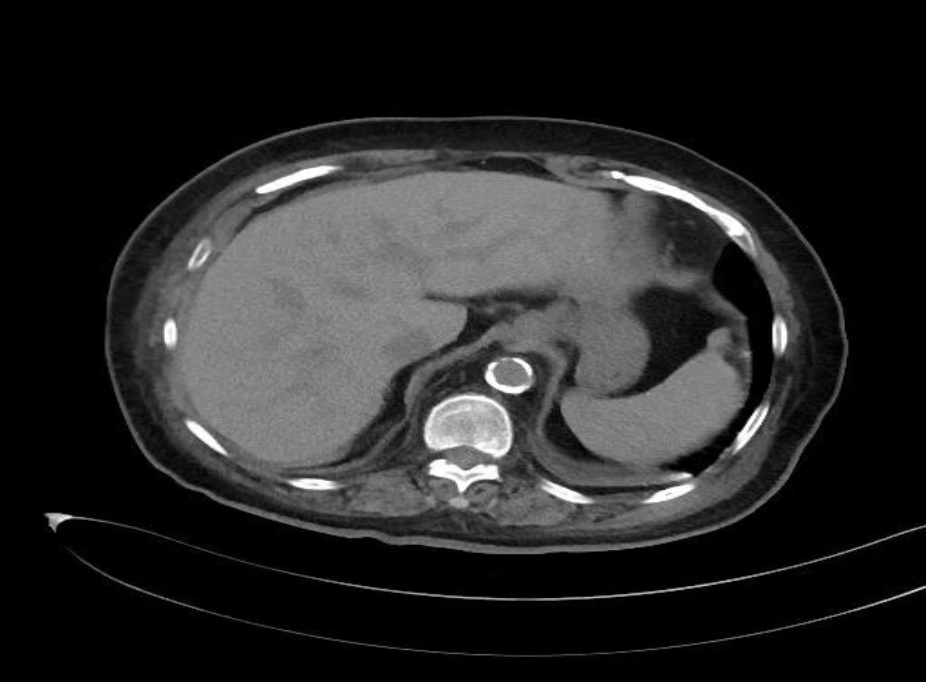

患者女性,72岁,诊断为2型糖尿病伴慢性肾功能不全,长期接受门诊血液透析治疗。本次透析2小时后突发持续性腹痛,伴呕吐3次,口服止痛药无效,遂于次日赴甘肃省人民医院普外科就诊。既往有高血压、糖尿病(30年)、冠状动脉粥样硬化性心脏病(冠脉支架植入术后1年)等病史,长期口服抗血小板药物。慢性肾衰竭10年,维持性血液透析10年,方案为每周3次,每次4小时。入院查体:血压126/74 mmHg,体温36.5℃,下腹部存在压痛、反跳痛及轻度肌紧张。腹部CT提示广泛肝门静脉积气,累及脾静脉、肠系膜上静脉、门静脉主干及肝内分支(见图1(a))。实验室检查白细胞计数升高(16.2 × 109/L),中性粒细胞百分比显著增高(93.80%),C-反应蛋白(76.50 mg/L),动脉血乳酸轻度升高(2.30 mmol/L)。因患者高龄,急性腹痛,既往2型糖尿病病史、长期血液透析,目前CT检查提示肝门静脉积气,经血管外科、重症医学科、心内科、内分泌科等多学科会诊,血流动力学稳定,且乳酸水平未显著升高,考虑肠坏死可能性较低,与患者家属充分沟通后,决定实施保守治疗。方案包括静脉输注头孢哌酮舒巴坦钠抗感染、禁食、补液、营养支持及低流量吸氧,治疗过程中密切监测病情变化。住院第6天复查腹部CT,显示肝内积气完全吸收(见图1(b))。患者出院后随访半年,一般情况稳定,未出现新发并发症。

(a) (b)

Figure 1. Plain abdominal CT scan images of the patient

1. 患者腹部CT平扫图像

图1(a):肝内多发积气影,沿门静脉及其分支走行,肝实质未见明显异常密度影;图1(b):治疗后肝内积气已消失,肝实质未见明显异常密度影。